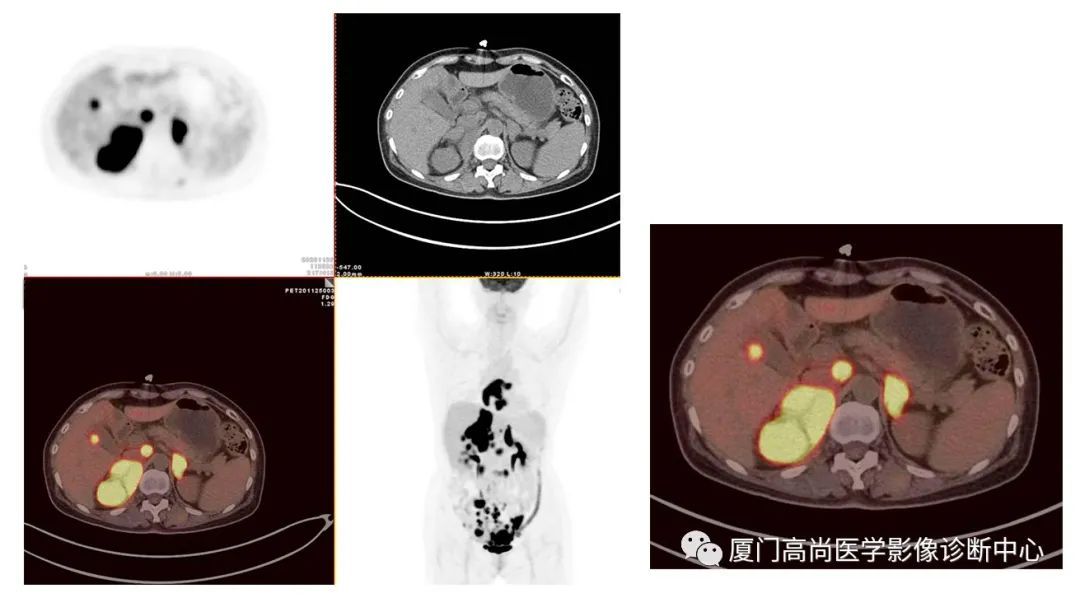

病例1:某男士,36歲,半年前摔傷,當(dāng)時無大礙,近幾個月來腰腿痛,并逐漸加重,消瘦10多斤。MRI檢查發(fā)現(xiàn)腰椎、骨盆 骨質(zhì)異常信號,查血各項腫瘤標(biāo)記物正常,因診斷不清而來做PET/CT檢查

淋巴瘤在骨骼、肝臟、脾臟、淋巴結(jié)表現(xiàn)

肝臟、脾臟、骨骼淋巴瘤病灶

PET/CT發(fā)現(xiàn) :全身多發(fā)淋巴結(jié)腫大,F(xiàn)DG攝取增高;肝臟、脾臟多發(fā)低密度結(jié)節(jié), FDG攝取增高;雙側(cè)扁桃體腫大,F(xiàn)DG攝取增高;全身多處骨骼破壞,F(xiàn)GD攝取增高;上述考慮為淋巴瘤

經(jīng)淋巴結(jié)穿刺活檢 :病理診斷為彌漫大B細(xì)胞淋巴瘤